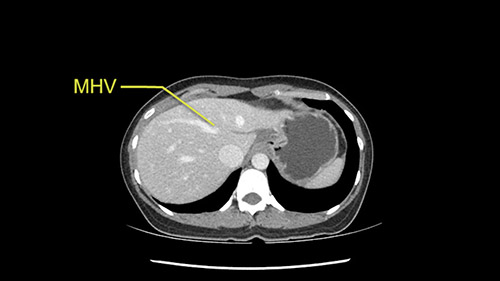

Anatomically, to plan for a left lateral segmentectomy, it’s relatively easy as far as liver surgery goes. I know that I'm going to be looking for the left hepatic vein which will be divided at some point either towards the end at the back near the vena cava or through the middle of the left lateral segment.

Preserve middle hepatic vein

So the issue with regards to resection. A left sided tumor. I believe I can see the falciform ligament right here so we’re looking at a resection of Segments 2, 3 of the left lobe of the liver. The left portal vein is right there. I think we’ll be wiser to take the left portal vein and therefore get well into Segment 4 and do a left hemihepatectomy. Certainly, one does not need to take the middle hepatic vein; it’s miles from the tumor.

The transection line will be a little more obvious. There’s a little patch of focal fat here in Segment 4b but we’ll describe the transection line probably through the mid portion of Segments 4a and b up to the top. Up at the top, the left hepatic vein can be taken. There’s a Segment 3 vein or the so-called falciform vein it’ll be rudimentary so I think we’ll be able to get around the left hepatic vein and leave the middle [hepatic] vein intact because it’s free of tumor.

The other option of course is to do an anatomical left hepatectomy. In that case, I will start mobilizing of course the left lobe and try to find the ligamentum venosum, take it down and go around the left hepatic vein. I think, importantly in these cases and in this case, as you can see in the venous phase, that’s clearly a moment to stop. Because the left hepatic vein is pretty close to the middle hepatic vein as sometimes it is so you may need to dissect a little bit the parenchyma on top of the left hepatic vein to be able to go around the left hepatic vein safely.